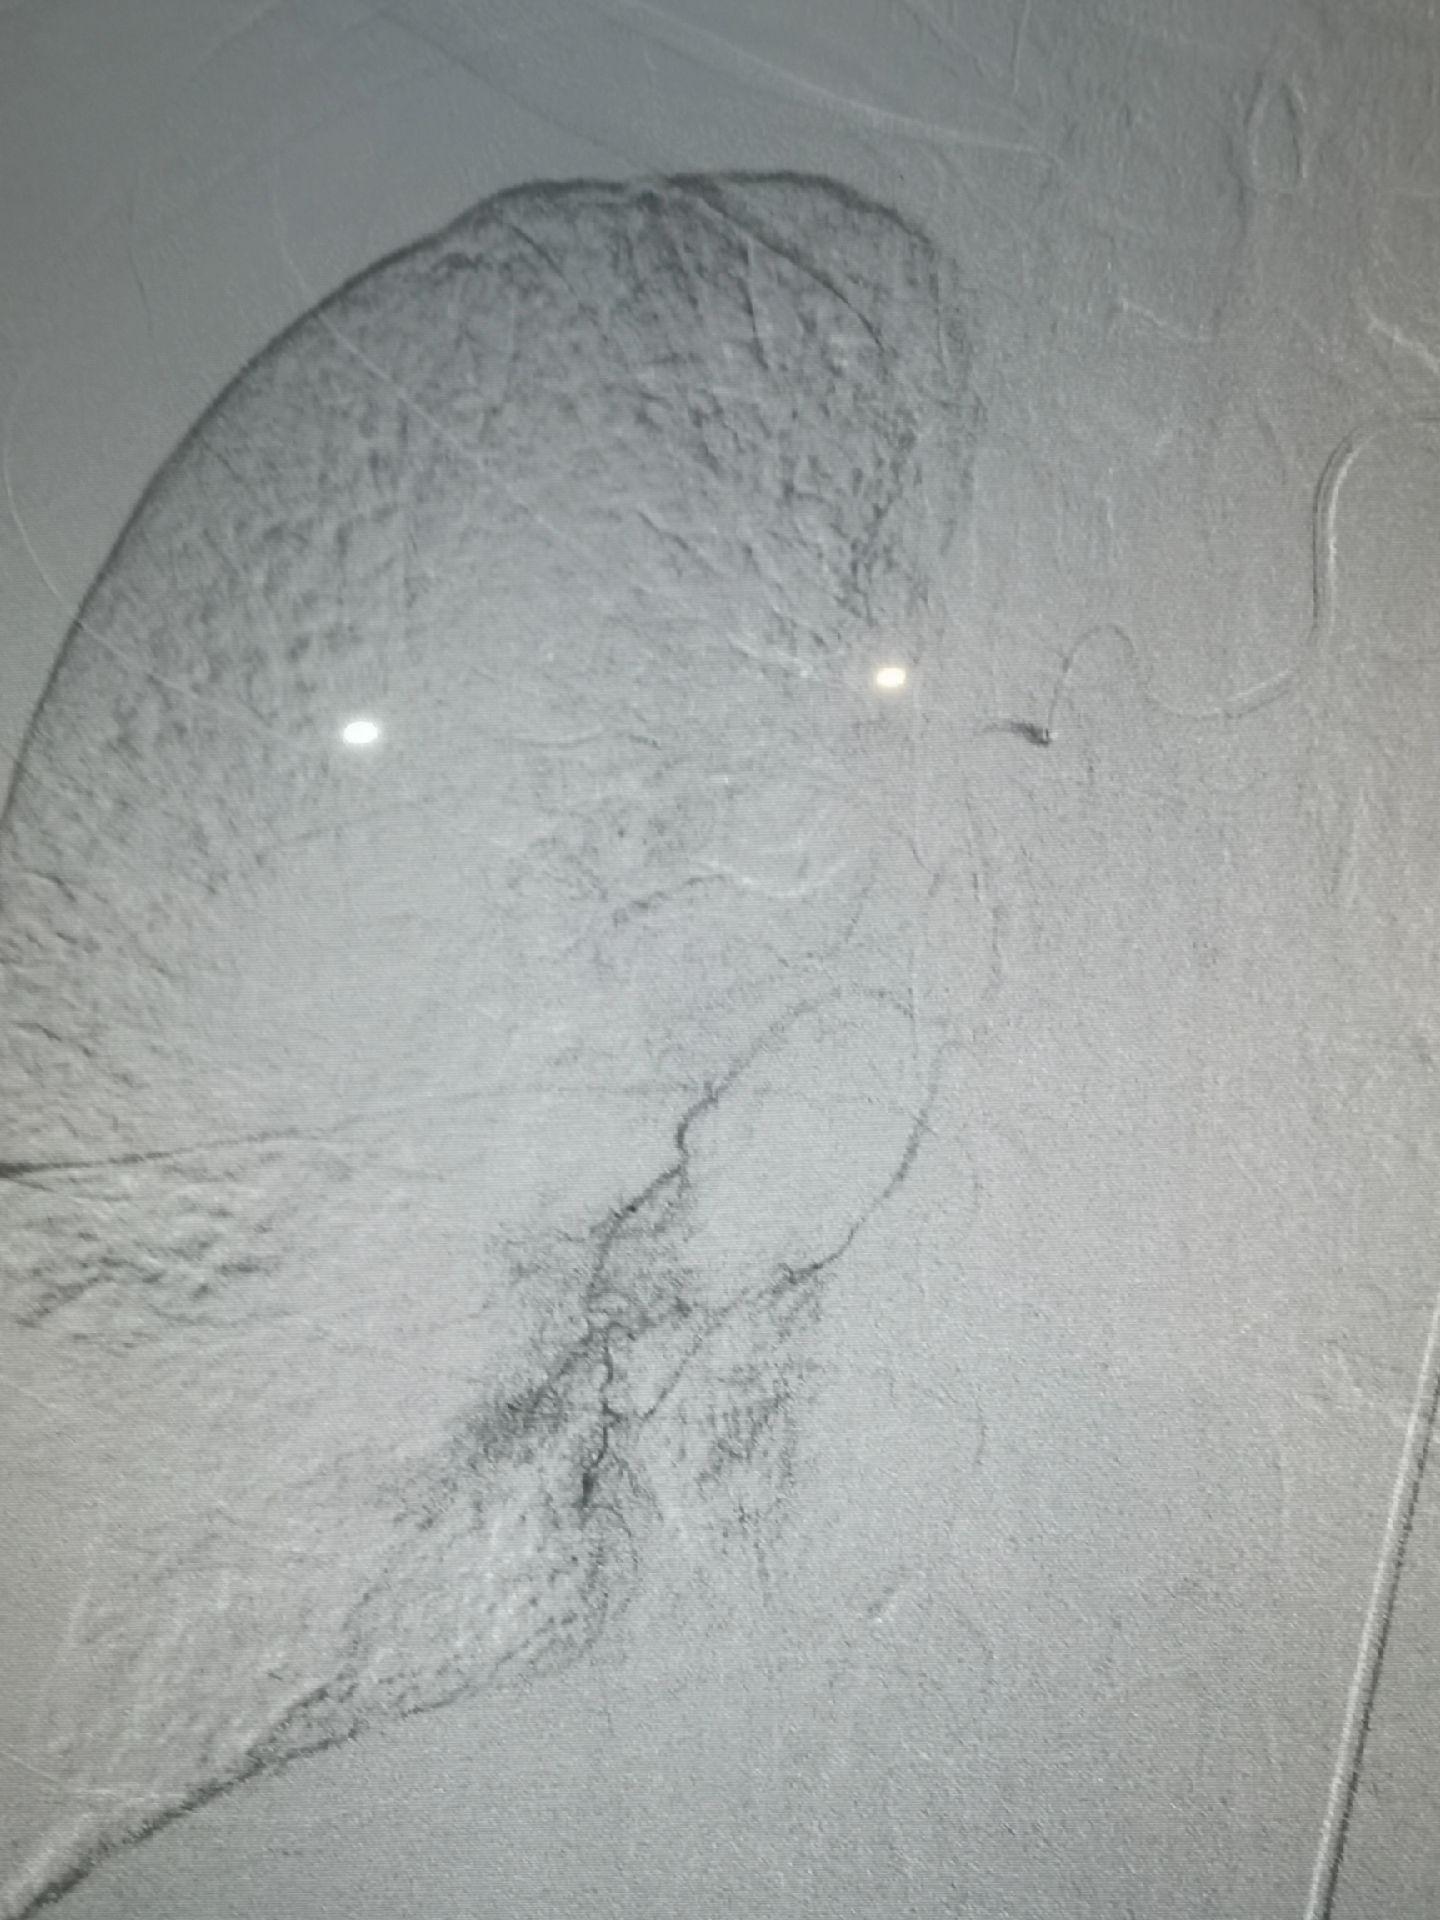

肺癌伴两肺转移,癌性淋巴管转移,体肺动脉化疗,支气管动脉联合肺动脉置管化疗。